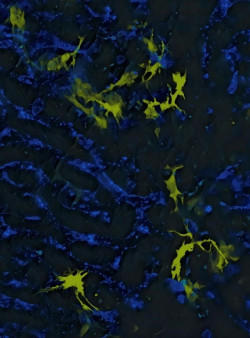

Identifican un grupo de células inmunitarias que esculpen las neuronas inhibidoras para regular el cableado del cerebro

Una investigación en ratones ha revelado cómo un subconjunto de células inmunes altamente especializadas modulan el cableado cerebral mediante sinapsis inhibidoras dirigidas con precisión. El trabajo profundiza la comprensión del repertorio versátil de microglia, las células inmunes del cerebro y los recolectores de basura residentes. Los resultados sientan las bases para el desarrollo de terapias para afecciones psiquiátricas y del neurodesarrollo marcadas por defectos en la función sináptica.